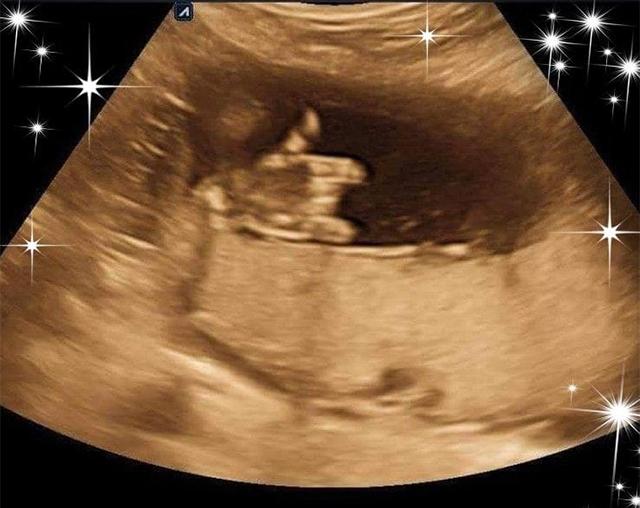

Hình ảnh siêu âm thai cực đáng yêu em bé nhà chị Hồng Lý.

Chia sẻ trên hội nhóm dành cho các mẹ bầu sinh con năm 2019, chị Hồng Lý đã đăng tải hình ảnh thai nhi ra tín hiệu rất lạ và đáng yêu. Em bé giơ ngón tay cái như nói con đang rất ổn với bố mẹ. Đi kèm với bức ảnh, chị Hồng Lý viết:

“- Mẹ: Con phải thật khỏe mạnh, đừng để mẹ lo đấy nhé!

- Mỡ: Ok mom”

Bức ảnh ngay lập tức nhận về rất nhiều lượt yêu thích với hành động cực đáng yêu của em bé.